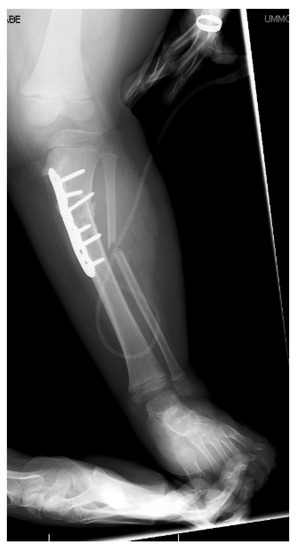

13. Osteotomies with Acute Correction

14. Hemi-Plateau Elevation Osteotomy